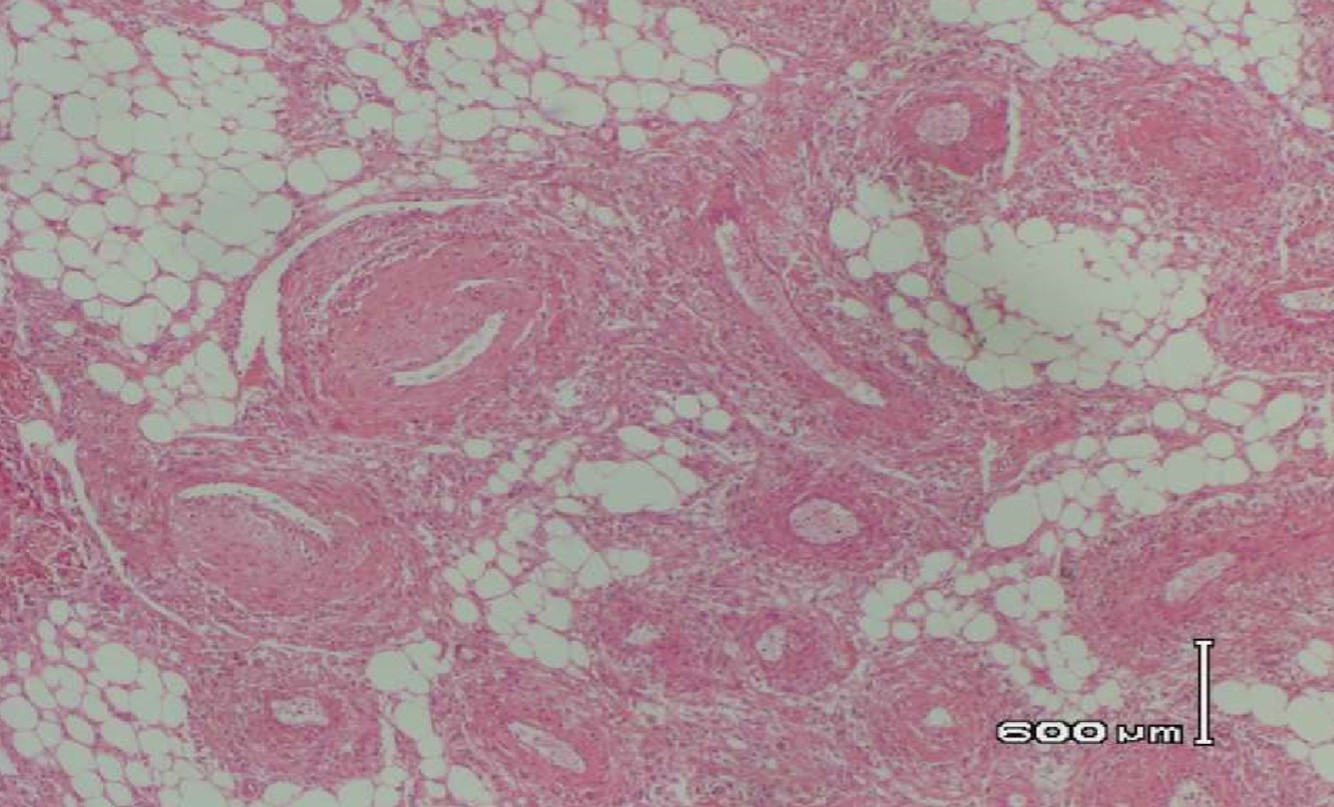

XANTHOGRANULOMATOUS PYELONEPHRITIS

- Often associated with large staghorn calculi of renal pelvis

- Many of these patients may have UTI, secondary to E. coli or Proteus

- May presents as a mass-like lesion

ANGIOMYOLIPOMA

- Sporadic or tuberous sclerosis

- tuberous sclerosis

- multifoca/bilateral, often associated with renal cysts/RCC

- Variants: regional nodal involvement, extrarenal disease (liver, spleen, lung), epithelioid AML

- Immunoreactive for actins and melanocytic markers

- Perivascular epitheliod cells - PEComa